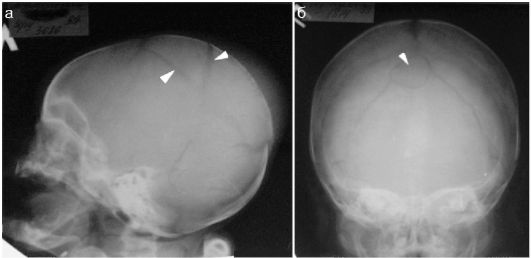

Переломы черепа у младенцев часто проявляются в виде трещин, представляющих собой линейные переломы. По их расположению, длине и ширине можно оценить степень серьезности травмы. Если края костного перелома расходятся, это может указывать на разрыв твердой оболочки мозга, что требует хирургического вмешательства.

Вдавленные переломы, при которых кость вогнута внутрь черепа, встречаются реже. Фрагменты кости могут сжимать мозг, и такие переломы у младенцев требуют хирургического лечения.

Младенцу также назначаются рентгенография, компьютерная томография и магнитно-резонансная томография.